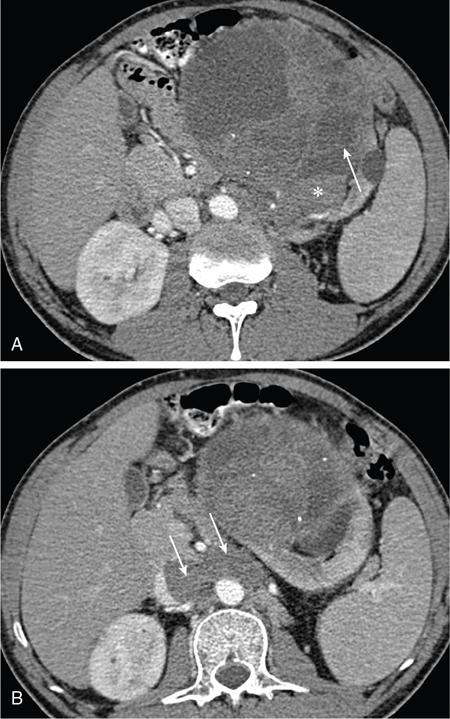

IMAGING OF RENAL MALIGNANCIES IN ADULTS Aparna Katdare, Palak Bhavesh Popat, Nilesh P. Sable, Ganesh Bakshi, Suyash Kulkarni Detection of renal masses has increased remarkably in recent times owing to wide-spread use of cross-sectional imaging. Imaging plays an important role in characterizing renal masses and is indispensable in treatment planning in renal malignancies. The most commonly encountered malignant renal masses in practice include renal cell carcinoma (RCC), urothelial carcinoma, lymphoma and metastases. Urothelial carcinoma and lymphoma have been covered in detail in separate chapters. RCC constitutes nearly 90% of all renal malignancies with a higher incidence in North America and Europe than India, Africa and China. With an increase in the number of cross-sectional studies performed, especially in Western population, the incidental diagnosis of RCC has increased in recent times, with such incidentally diagnosed lesions presenting at earlier stages with better prognosis and reduced rates of recurrence. The median age of presentation of RCC is 64 years according to the Surveillance, Epidemiology and End Results (SEER) program database and almost a decade earlier in Indian population, with a definite increasing risk of RCC with increasing age. Males are affected about 2–3.5 times more than females. In the Indian population, patients have been seen to present at a later stage as compared to the Western population. Amongst the various postulated risk factors, there is convincing evidence that smoking, hypertension, obesity and acquired renal cystic disease increase the risk of RCC. Alcohol intake and physical activity have been found to be associated with reduced risk of RCC. Trichloroethylene and cadmium exposure have been postulated as likely causes as well. Two to four per cent of RCCs are hereditary, with association of various genetic disorders such as Von Hippel Lindau (VHL) syndrome, hereditary papillary renal carcinoma, hereditary leiomyomatosis RCC, Birt-Hogg-Dube syndrome, chromosome 3 translocation and tuberous sclerosis (TCS1, TCS2). The WHO classification of 2016 (Table 11.25.1.1) stratifies tumours of the kidney into different subtypes based on cytoplasmic and architectural features, tumour location, background renal disease and molecular alterations. Clear cell renal cell carcinoma Multilocular cystic renal neoplasm of low malignant potential Papillary renal cell carcinoma Hereditary leiomyomatosis and renal cell carcinoma-associated renal cell carcinoma Chromophobe renal cell carcinoma Collecting duct carcinoma Renal medullary carcinoma MiT family translocation renal cell carcinomas Succinate dehydrogenase-deficient renal carcinoma Mucinous tubular and spindle cell carcinoma Tubulocystic renal cell carcinoma Acquired cystic disease-associated renal cell carcinoma Clear cell papillary renal cell carcinoma Renal cell carcinoma, unclassified Papillary adenoma Oncocytoma 8310/3 8316/1a 8260/3 8311/3* 8317/3 8319/3 8510/3a 8311/3a 8311/3 8480/3a 8316/3a 8316/3 8323/1 8312/3 8260/0 8290/0 Metanephric adenoma Metanephric adenofibroma Metanephric stromal tumour 8325/0 9013/0 8935/1 Nephrogenic rests Nephroblastoma Cystic partially differentiated nephroblastoma Paediatric cystic nephroma 8960/3 8959/1 8959/0 Clear cell sarcoma Rhabdoid tumour Congenital mesoblastic nephroma Ossifying renal tumour of infancy 8964/3 8963/3 8960/1 8967/0 Leiomyosarcoma Angiosarcoma Rhabdomyosarcoma Osteosarcoma Synovial sarcoma Ewing sarcoma Angiomyolipoma Epithelioid angiomyolipoma Leiomyoma Haemangioma Lymphangioma Haemangioblastoma Juxtaglomerular cell tumour Renomedullary interstitial cell tumour Schwannoma Solitary fibrous tumour 8890/3 9120/3 8900/3 9180/3 9040/3 9364/3 8860/0 8860/1a 8890/0 9120/0 9170/0 9161/1 8361/0 8966/0 9560/0 8815/1 Cystic nephroma Mixed epithelial and stromal tumour 8959/0 8959/0 Well-differentiated neuroendocrine tumour Large cell neuroendocrine carcinoma Small cell neuroendocrine carcinoma Phaeochromocytoma 8240/3 8013/3 8041/3 8700/0 Renal haematopoietic neoplasms Germ cell tumours The morphology codes are from the International Classification of Diseases for Oncology (ICD-O) {917A}, Behaviour is coded/0 for benign tumours; /1 for unspecified, borderline or uncertain behaviour; /2 for carcinoma in situ and grade III intraepithelial neoplasia; and /3 for malignant tumours. The classification is modified from the previous WHO classification (756A), taking into account changes in our understanding of these lesions. aNew code approved by the IARC/WHO Committee for ICD-O. Of these, the most common entity is the clear cell subtype, while papillary and chromophobe subtypes are less common. The different subtypes show varied biological behaviour, treatment response and prognosis. The 2017 guidelines by American Urological Association (AUA) as well as 2019 guidelines by European Society of Medical Oncology (ESMO) recommend multiphase cross-sectional imaging by either CT or MRI for renal mass characterization and staging. AUA 2017 guidelines recommend renal mass characterization on the basis of tumour complexity, contrast enhancement and presence or absence of fat. MRI has an upper hand over CT in characterizing subtle mass enhancement, cystic lesions and lesions less than 2 cm. ESMO recommends contrast-enhanced CT study of the chest, abdomen and pelvis for renal mass staging. Bone scan and brain CT or MRI can be considered if indicated by clinical or laboratory investigations. For characterization of renal masses, a multiphase CT or MRI study is recommended. CT study constitutes an unenhanced study followed by contrast injection and acquisition of corticomedullary phase at 40 seconds, nephrographic phase at around 100 seconds and delayed phase at around 5 minutes. MRI protocol includes T2-weighted single-shot fast spin-echo 2D sequences, axial T1-weighted 2D sequence with in-phase and opposed-phase gradient echo imaging, precontrast and postcontrast imaging with a 3D T1-weighted spoiled gradient recalled sequences in corticomedullary phase at 30 seconds, nephrographic phase at 100 seconds, 180–210 seconds and delayed phase imaging at 5 minutes and diffusion-weighted imaging with multiple b-values 0–50, 400–500 and 800–1000 s/mm2. The ACR White Paper on CT imaging of incidental renal mass recommends using the following descriptors for characterizing renal masses: Given the prognostic implications, it is worthwhile for radiologists to know the imaging features that may help discriminate between the common histological subtypes of RCC on various imaging modalities. This is the most common histological type of RCC, accounting for about 70% of cases. These are exophytic tumours with a heterogeneous appearance due to the presence of necrosis, intratumoural haemorrhage, cystic components with septations and calcific foci and hence have a more heterogeneous appearance on cross-sectional imaging than the other subtypes (Fig. 11.25.1.1). Necrosis is seen more often in larger masses and higher tumour grades (Fig. 11.25.1.2). On CT, depending on the tumour composition, these are seen as heterogeneous lesions, show marked contrast enhancement in the corticomedullary phase with washout on nephrogenic phase (Fig. 11.25.1.2). On MRI, these characteristically show high signal intensity on T2W sequences (Fig. 11.25.1.3). The presence of intracytoplasmic fat in the clear cells of the tumour is reflected in the loss of signal in opposed phase images on chemical shift imaging, which is seen in nearly 60% of these tumours. A pseudocapsule may be seen, which is best appreciated on T2-weighted imaging on MRI; the presence of a pseudocapsule has a high negative predictive value for perinephric extension (Figs. 11.25.1.3 and 11.25.1.4). Conversely, larger tumours with higher grades often have interrupted pseudocapsule and hence tend to be irregular, spread into the perinephric fat with renal vein and inferior vena cava (IVC) invasion (Figs. 11.25.1.5 and 11.25.1.6). On diffusion-weighted imaging, clear cell RCCs have been seen to have higher ADC values than nonclear cell RCCs, and lower-grade tumours have been seen to have higher ADC values than higher-grade tumours. The clear cell variant has worse prognosis than the papillary and chromophobe subtypes, presenting at a more advanced stage and being more likely to recur or metastasize (Fig. 11.25.1.7), with lower 5-year survival rates at 44%–69% as compared to 78%–92% for the other two. Papillary RCC comprises about 10%–15% of RCCs. These are slow-growing tumours and hence are well-marginated in contrast to clear cell RCC. As they are hypovascular, their enhancement on CT is significantly less than clear cell RCC (Fig. 11.25.1.8). These show characteristically low signal on T2W images on MRI (Fig. 11.25.1.9). Intracytoplasmic or macroscopic fat is less often seen on MRI imaging as compared to the clear cell variants. Larger tumours tend to be more heterogeneous (Fig. 11.25.1.10). These tumours may sometimes show cystic appearances, mural projections or blood degradation products. Calcifications are more common in papillary variants than clear cell RCC. Multifocality and bilaterality are also more common in these tumours than clear cell variants. These account for about 5% of RCCs. These are less aggressive, more homogeneous and hypovascular lesions than clear cell variants, with intensity of contrast enhancement on cross-sectional imaging being midway between clear cell and papillary variants. They show low to intermediate T2 signals on MRI. A characteristic feature is the presence of a central scar and spoke-wheel enhancement, the latter being a histopathological and imaging similarity between these tumours and oncocytoma (Fig. 11.25.1.11). Other subtypes of RCC are much less common but some may show distinct imaging findings. Multilocular cystic RCCs have excellent prognosis and lack mural nodules within the cystic components, unlike clear cell RCCs with cystic degeneration which show mural nodules. Collecting duct carcinomas, on the other hand, are aggressive tumours with poor prognosis and have medullary origin, and therefore appear similar to transitional cell carcinomas on imaging. Medullary RCCs are associated with sickle cell disease and sickle cell trait and are seen as infiltrating intracalyceal obstructive lesions with associated nodal disease. The imaging work-up of a suspected RCC is aimed at: Localized renal cancer is defined as a disease confined to the renal capsule and refers mainly to stage I and II disease. Nearly 70% of RCCs, especially the lower-stage lesions, are incidentally diagnosed on cross-sectional imaging. Also, amongst incidentally diagnosed renal lesions less than 4 cm in size, about 20% turn out to be benign on histopathology. Asymptomatic incidentally diagnosed small renal masses have an indolent course and better prognosis. Nephron-sparing surgery (NSS) has gathered momentum in recent years due to promising results and prognoses in small lesions. The 2017 AUA guidelines for localized renal masses describe restricted and well-defined indications for radical nephrectomy, bigger role of nephron-sparing procedures such as partial nephrectomy, tumour enucleation and thermal ablation, as well as increasing role for biopsy as well as active surveillance of such lesions. Hence, imaging findings in these lesions become critical in charting management of these patients. The imaging features of common histopathological subtypes of RCCs have already been discussed above. Signal intensity on T2W images and corticomedullary phase enhancement have been seen to be independent predictors of clear cell and papillary RCCs. Further, T2 signal homogeneity can be a predictor for slower growth rate. Hence, in general, multiparametric MRI studies have been shown to be effective in small renal mass characterization and can subsequently guide decisions regarding biopsy, surgery or surveillance. CT is a good alternative in patients with contraindication to MRI. For cystic renal lesions, the Bosniak classification, which stratifies the risk of neoplasia in cystic renal lesions based on the complexity of their appearance (wall thickness, septations, solid component), can be used effectively to decide further course of management. The Bosniak classification originally applies to CT findings but can logically be extrapolated to MRI, USG and Contrast Enhanced Ultrasound (CEUS) as well. Bosniak I and II cysts are benign while Bosniak IIF, III and IV cysts show progressively increasing risk of neoplasia. Given the more indolent course of cystic RCCs as compared to solid lesions and possible complications of interventions, lately there has been a case for even the type III and IV cysts, which previously would be operated, to be followed up, especially if patient has existing comorbidities or if the solid component is minimal. Initial follow-up would be at 6 months, followed by annual imaging. AUA 2017 guidelines recommend considering renal mass biopsy if haematologic, metastatic, inflammatory or infectious aetiology is suspected. Once the need for surgery is established in a localized disease, NSS may be considered for stage Ia and Ib disease. To predict perioperative outcomes in NSS, various scoring systems have been proposed for preoperative renal mass evaluation, such as R.E.N.A.L. nephrometry score, PADUA score (Preoperative aspects and dimensions used for anatomical classification), C-index method and mathematical tumour contact surface area (CSA). The popular R.E.N.A.L. nephrometry score takes into account various tumour descriptors that help decide the technical feasibility of NSS and predict surgical outcomes. These include tumour radius, exo/endophytic location, nearness to collecting system or renal sinus, anterior/posterior location and location with reference to polar lines. These descriptors need to be commented upon diligently while reporting renal masses (Table 11.25.1.4). Higher scores are seen to correlate with ischaemia time, postoperative urologic complications, higher grade and mortality. These include organ-confined tumours more than 7 cm in size, or tumours of any size which show regional nodal involvement and/or invasion of perinephric tissues but confined to Gerota’s fascia. These include renal vein and IVC invasion (luminal and mural). Generally, radical nephrectomy is recommended by the National Comprehensive Cancer Network (NCCN) in stage II and III RCCs. Both CT and MRI are effective in diagnosing locally advanced disease in RCC. The loss or interruption of pseudocapsule is seen in more infiltrative and aggressive disease and is best seen on MRI. Local infiltration may be in the form of contiguous spread to perinephric tissues or discrete deposits in perinephric fat (Fig. 11.25.1.15). IVC or renal vein invasion could be in the form of intraluminal thrombosis or invasion of the vessel wall and have implications on surgical approach and outcomes. Tumour thrombus can be distinguished from bland thrombus by confirming vascularity within the thrombus on imaging. Doppler evaluation, CEUS, CT and MRI can all be helpful for the same. MRI is better than other modalities for venous evaluation, especially for mural invasion and IVC invasion (Figs. 11.25.1.16 and 11.25.1.17). Right-sided tumours, anteroposterior IVC diameter of 2.4 cm or more at the level of renal hilum and complete IVC occlusion at this level are associated with higher risk of IVC resection. About 16% of patients with RCC have metastases at diagnosis and about 20%–30% of patients operated for local disease develop recurrence or metastases at a later date. The recurrent disease occurs most commonly within 3 years of diagnosis and uncommonly even later in young patients or large tumours. The most common sites of metastases from RCC are lungs, liver, bones, nodes, adrenals and brain. CT scan is the preferred modality for primary staging and surveillance for metastases because of its widespread availability and versatility for diagnosing bone and soft tissue lesions. MRI is preferred for looking for recurrence in postablative lesions, wherein these are seen as new enhancing lesions or show increase in the size of preexisting enhancing components. 18FFluorodeoxyglucose – Positron Emission Tomography (PET)/CT and PET/MRI may be helpful to look for metastatic disease as well. 18FSodium fluoride – PET/CT has been found to be better than CT and bone scan in detecting osseous metastases. RCC is a relatively radiation-resistant tumour, and treatment options tilt in favour of surgical procedures for localized and locally advanced diseases. For metastatic disease, post-risk assignment, the treatment has to be planned. Treatment can be offered as per size and the clinical stage.